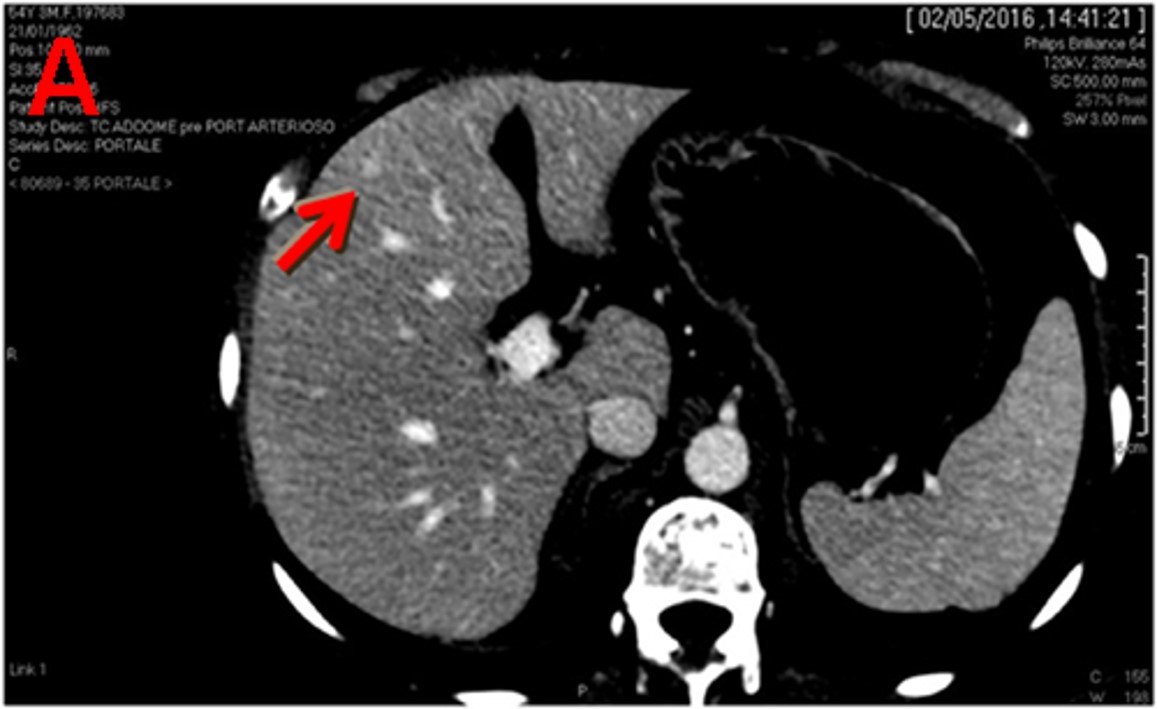

CT and MR images in a 37-year-old male with poorly-differentiated HCC with histological capsule. METAVIR score of the background liver was F3. In contrast-enhanced CT, a 49-mm observation shows (a) nonrim APHE on arterial phase and (b) nonperipheral washout with an enhancing capsule on equilibrium phase. In gadoxetic acid-enhanced MRI, a 48-mm observation shows (c) nonrim APHE on arterial phase, (d) nonperipheral washout on portal venous phase, and (e) TP hypointensity with suspicion of an enhancing capsule on transitional phase. Hepatobiliary phase image clearly shows (f) a nonenhancing capsule surrounding the observation.

(a) unenhanced, (b) Arterial, (c) portal, and (d) delayed phases. After intravenous contrast administration, the nodule shows stable peripheral rim-like enhancement (arrow).

T1 C+ (Gd)

heterogeneous enhancement with progressive filling

irregular flame-shaped pattern

Target appearance

Target appearance

Computed tomography (CT) scan performed in April 2016 shows three liver lesions (LLs) in arterial phase. a. The arrow indicates LL (diameter: 7 mm) with contrast enhancement suspected of metastasis at 4th segment.